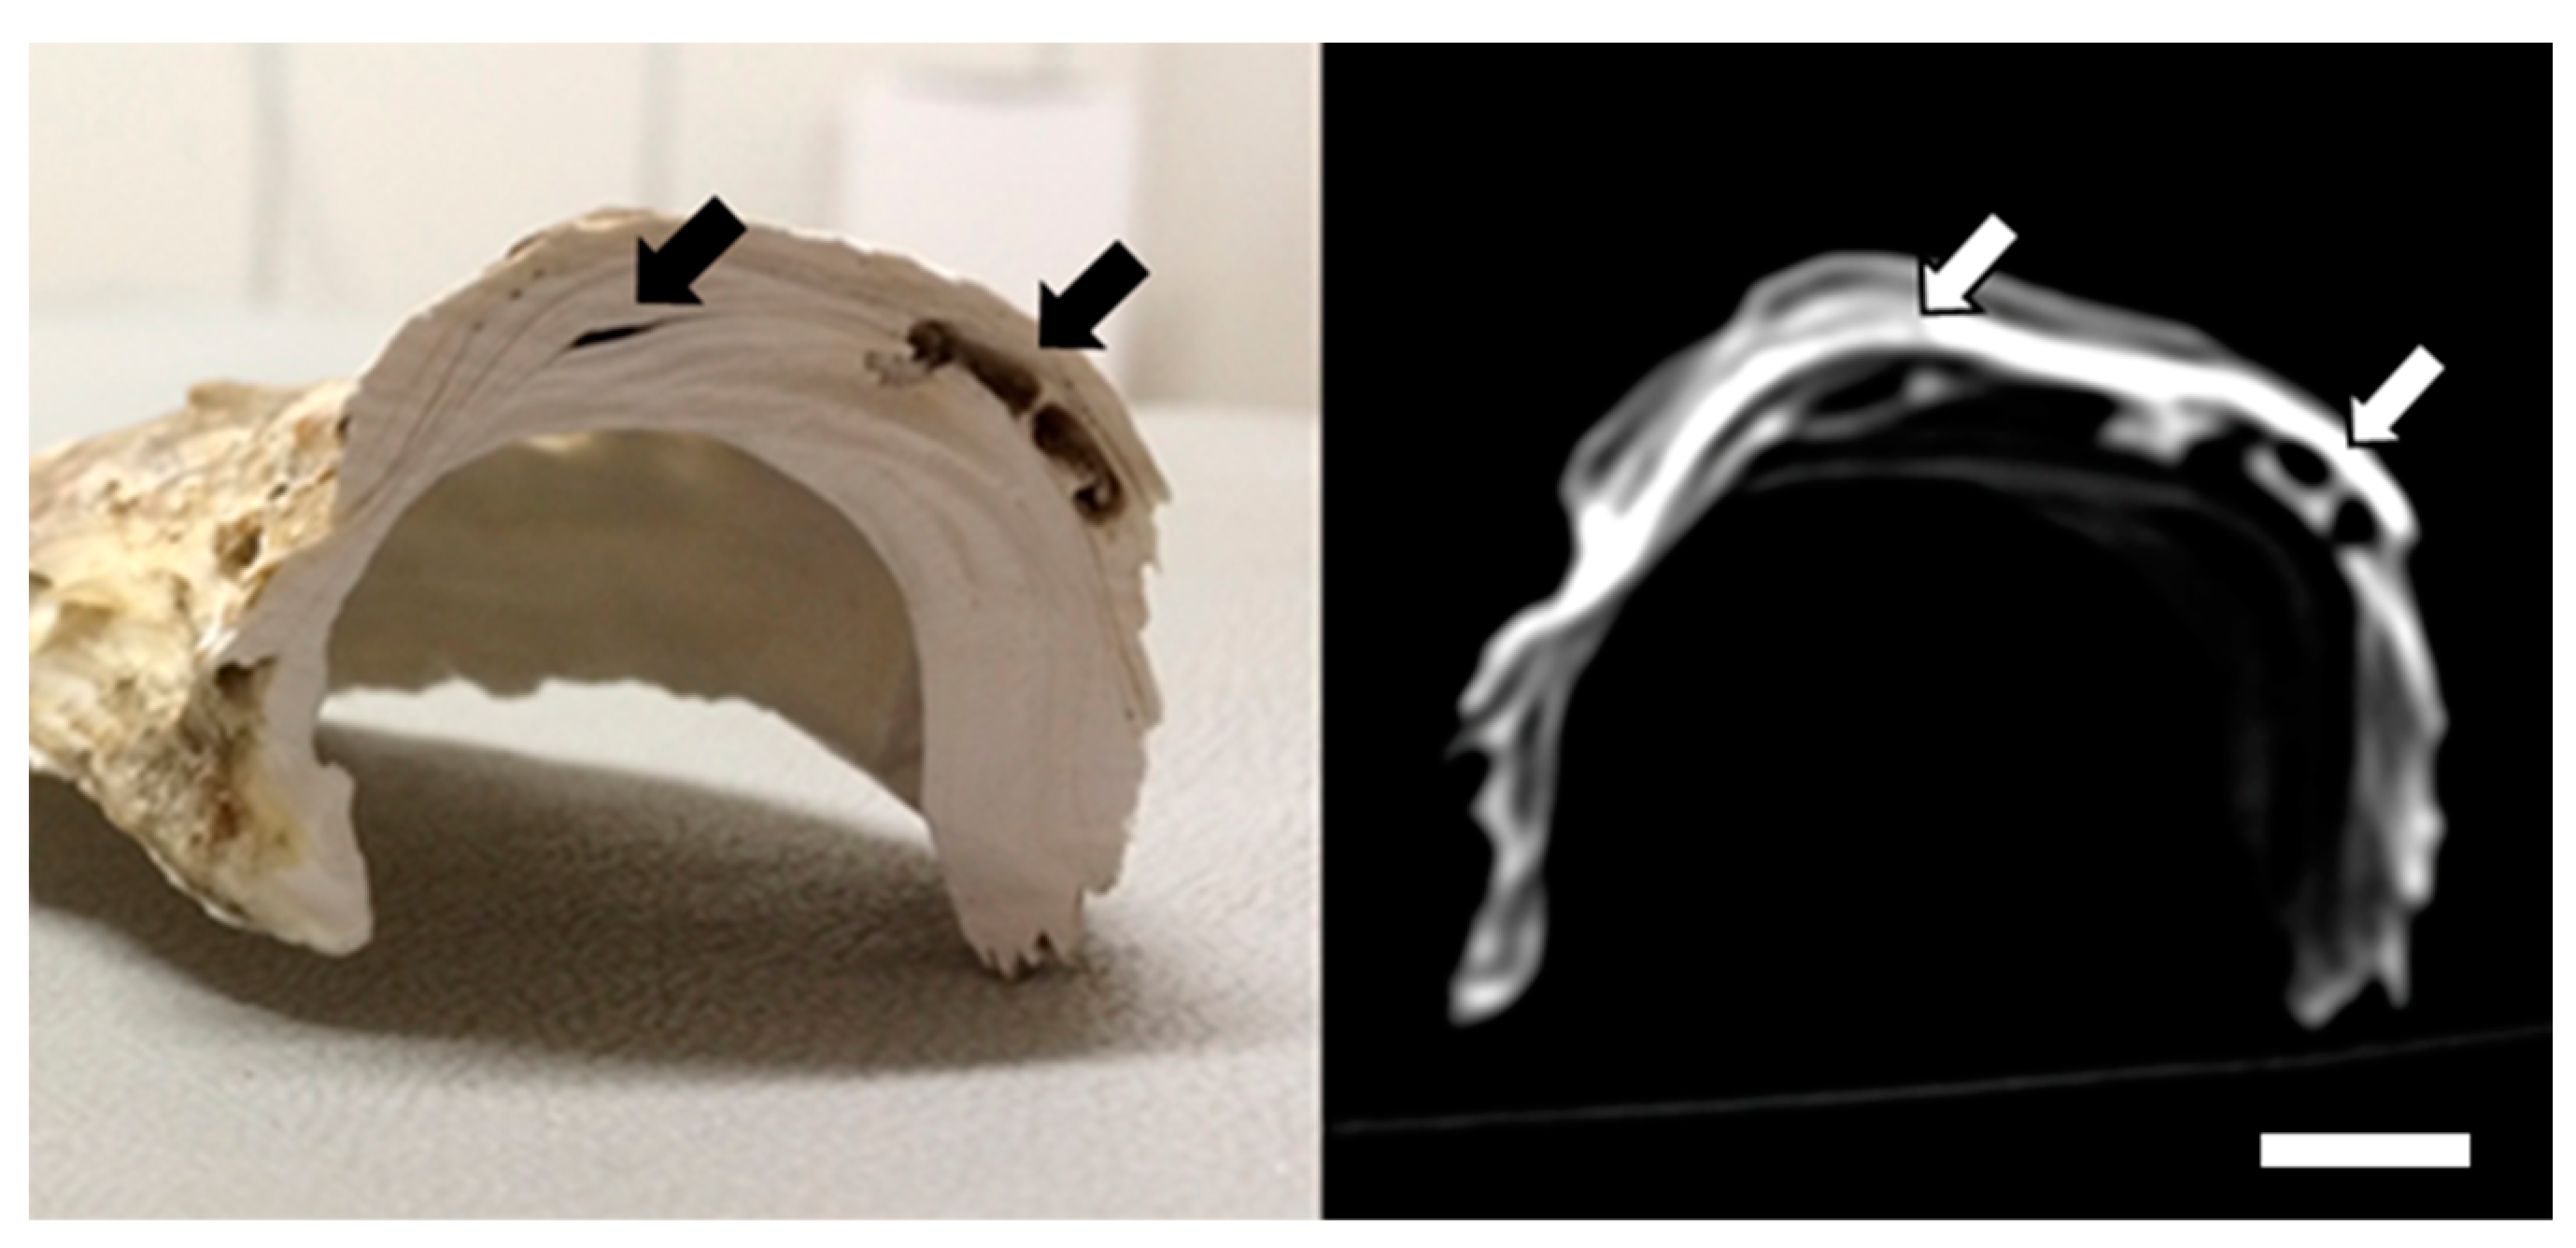

3.2. Macroscopic Findings

4. Discussion